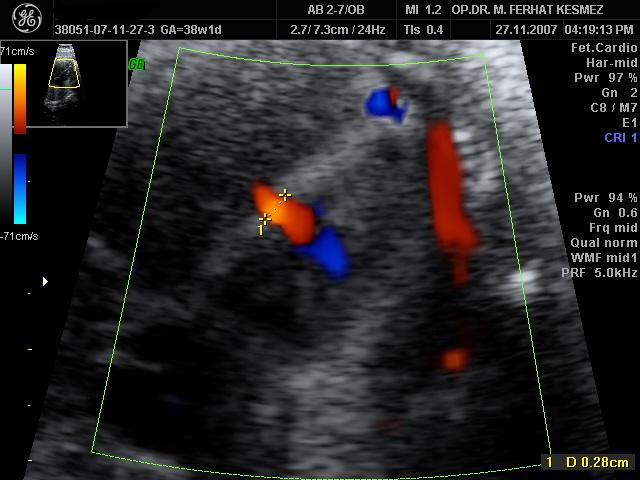

Op. Dr. Muhammed Ferhat Kesmez

Kadın Hastalıkları, Doğum ve Tüp Bebek Uzmanı

• Op. Dr. Muhammed Ferhat Kesmez, kadın sağlığı, gebelik takibi, doğum ve tüp bebek tedavisi alanlarında uzmanlaşmış deneyimli bir hekimdir. Kısırlık (infertilite) tedavisinde en son teknolojileri kullanarak çiftlere anne-baba olma yolculuklarında rehberlik eder. Bireysel ve bilimsel yaklaşımlarla hastalarına özel tedavi yöntemleri sunarak sağlıklı gebelik süreçleri sağlamayı hedefler. Güvenilir ve hasta odaklı hizmet anlayışıyla, modern tıbbın sunduğu yenilikleri hastalarına ulaştırmaktadır.